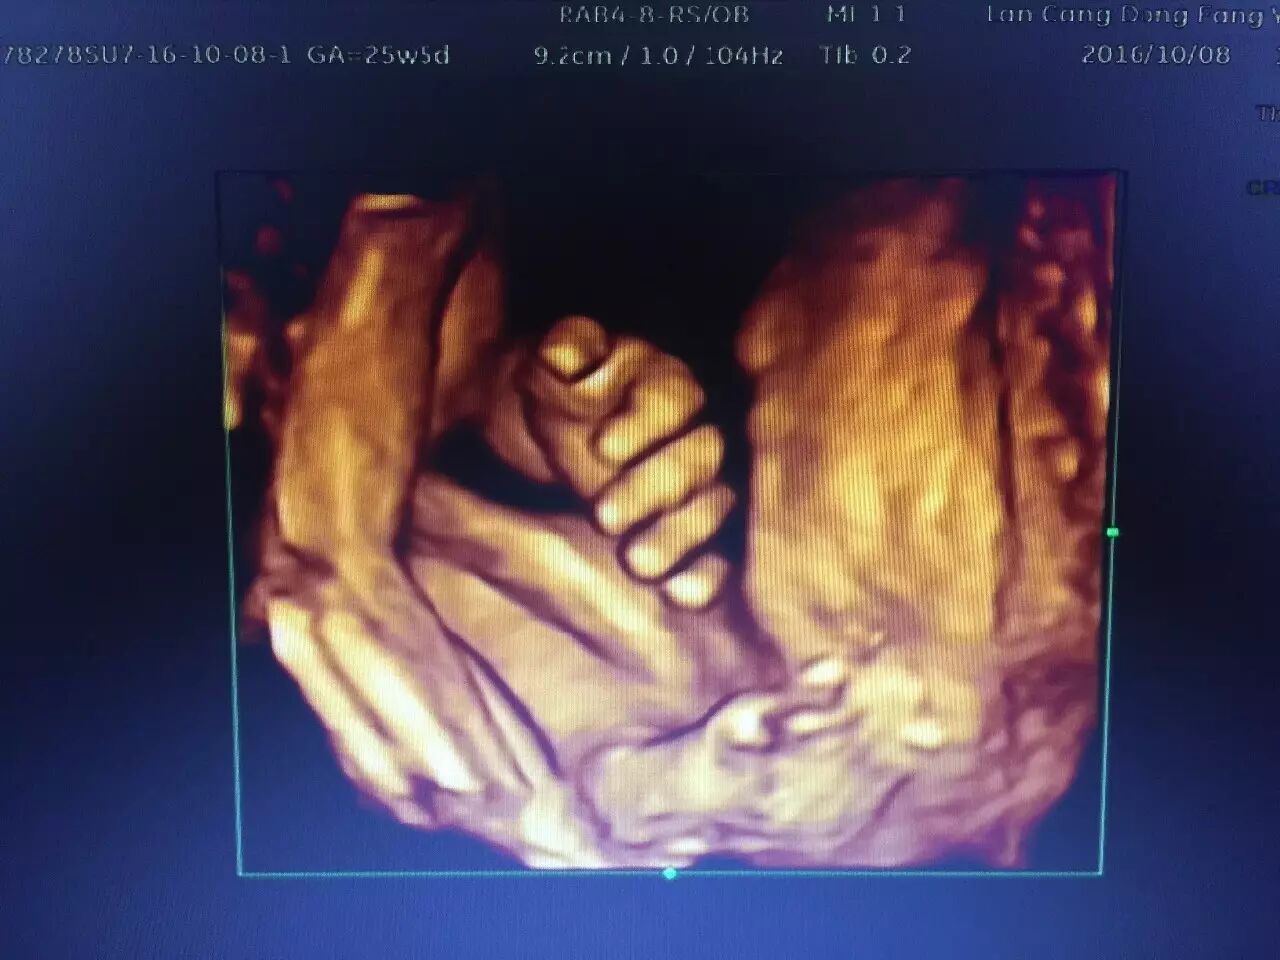

其优点一改既往二维超声中黑白色调的静态平面图像,而变成有色彩的立体动态的人体器官(包括胎儿)的实时活动图像,使医生的诊断更精确、可靠

(上图为胎儿脊柱连续完整)